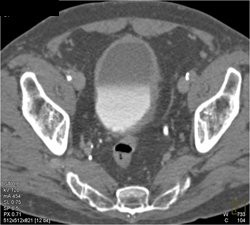

Normal CT Urogram